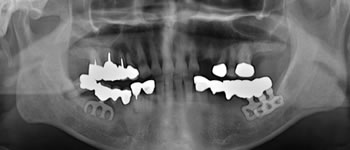

全顎短期治療 症例

初診時